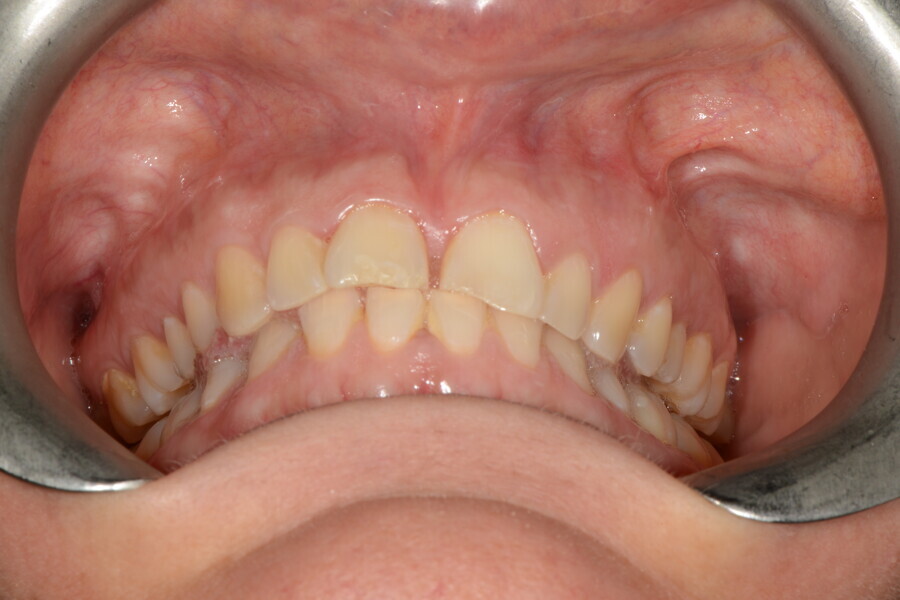

The 58-year-old patient wished to improve his oral aesthetics and function, complaining of mobility of the posterior teeth and wear of the anterior teeth. After data collection, a very complex situation was identified (Figs. 11–13):

1. severe periodontitis with poor prognosis of some teeth;

2. anterior crossbite;

3. severe wear mainly of the anterior teeth and compensatory eruption;38

4. atypical swallowing and lower posture of the tongue at rest;

5. masticatory dysfunction during the mastication test; and

6. no significant signs of temporomandibular disorder.